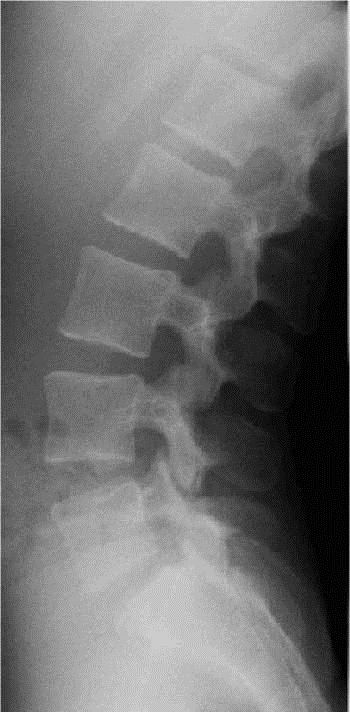

PROFIL

– – Le patient est positionné en rectitude de profil

– – Il est positionné en profil droit ou gauche

– – L’épaule est contre la table et le bassin contre la table

– – Les talons sont joints et en appuis symétrique

– – Le plan sagittal médian est parallèle au plan de la table

– – Les bras sont croisés en avant

RAYON DIRECTEUR

– – Il est centré sur L3 : c’est à dire 2 cm au- dessus des crêtes iliaques

CRITERES DE REUSSITE

– – On doit voir les 5 lombaires

– – Les disques doivent être enfilés

ANATOMIE RADIOLOGIQUE

- – Articulaire supérieure

- – Pédicule

- – Apophyse transverse

- – Articulaire inférieure

- – Epineuse

- – Bord postérieur du canal rachidien

- – Bord supérieur des lames

- – Bord inférieur des lames

- – Isthme

IMAGE NORMALE